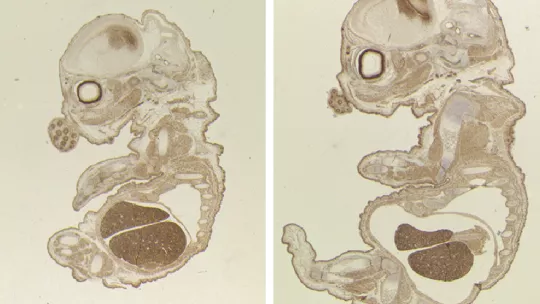

En ratones sin TLK2, el embrión es más pequeño pero los investigadores no observan defectos morfológicos y la placenta también es más pequeña. Son los fallos en la placenta la causa de la muerte del embrión a los 15 días de los 20 de gestación. Los científicos detectan una reducción en la expresión de genes importantes para la proliferación o supervivencia de trofoblastos -grupo de células especializadas que provee nutrientes al embrión- con efectos en la funcionalidad de la placenta.